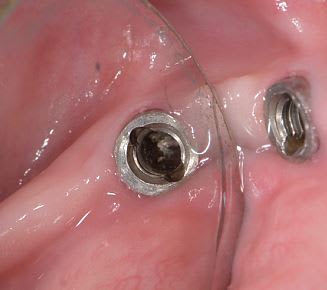

auriez-vous un idée de la marque de cet implant posé il y a plus de vingt ans.

Steri-oss

Composants prothétiques pour ainsi dire introuvables maintenant…..désolé mais songe plutôt à déposer…..